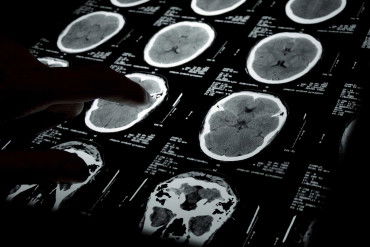

Did she have a brain abnormality before the surgery that could have caused a seizure? If no such condition exists, then the husband will need to consider whether their wife has been the victim of anoxia or hypoxia. This type of medical negligence happens when a patient is put under anesthesia for too long and thus starts to loose oxygen to the brain. This can lead to seizures. Getting to the root cause of this condition will help a husband figure out why their wife is having seizures after surgery.